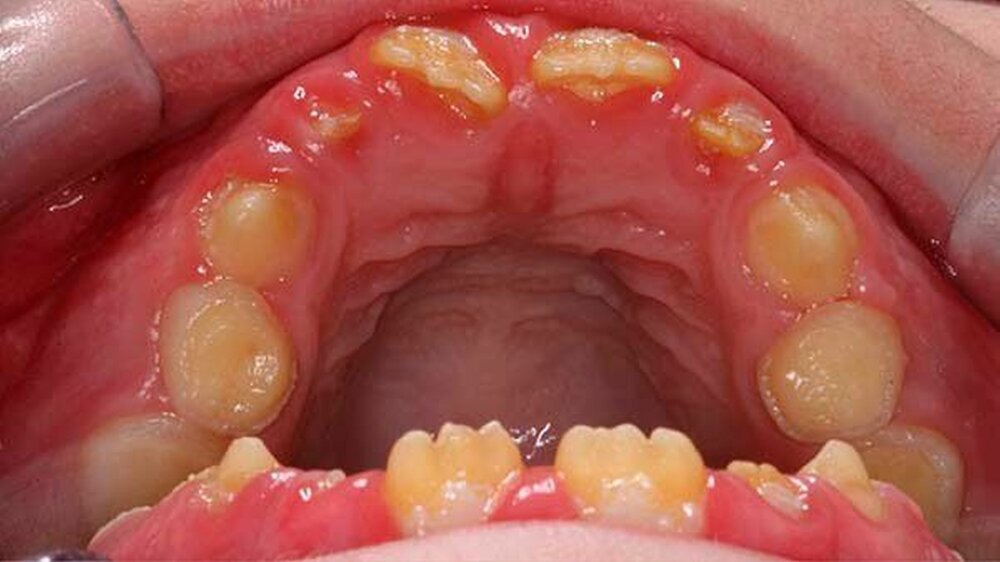

Der klinische Befund zeigte an beiden Dentitionen eine rauhe, zum Teil verminderte, bis fehlende Schmelzdicke und eine teilweise bräunliche Zahnverfärbung. Letztere wurden auch durch exogene Pigmenteinlagerung verursacht (Abbildung 1b und Abbildung 2).

Im radiologischen Befund konnte teilweise ein Kontrast zwischen Schmelz und Dentin festgestellt werden, jedoch war bei beiden Dentitionen eine verminderte Schmelzdicke ersichtlich (Abbildung 4). Auf Grund der radiologischen und klinischen Beurteilung konnte die Diagnose Amelogenesis imperfecta generalisata vom hypoplastischen Typ gestellt werden.